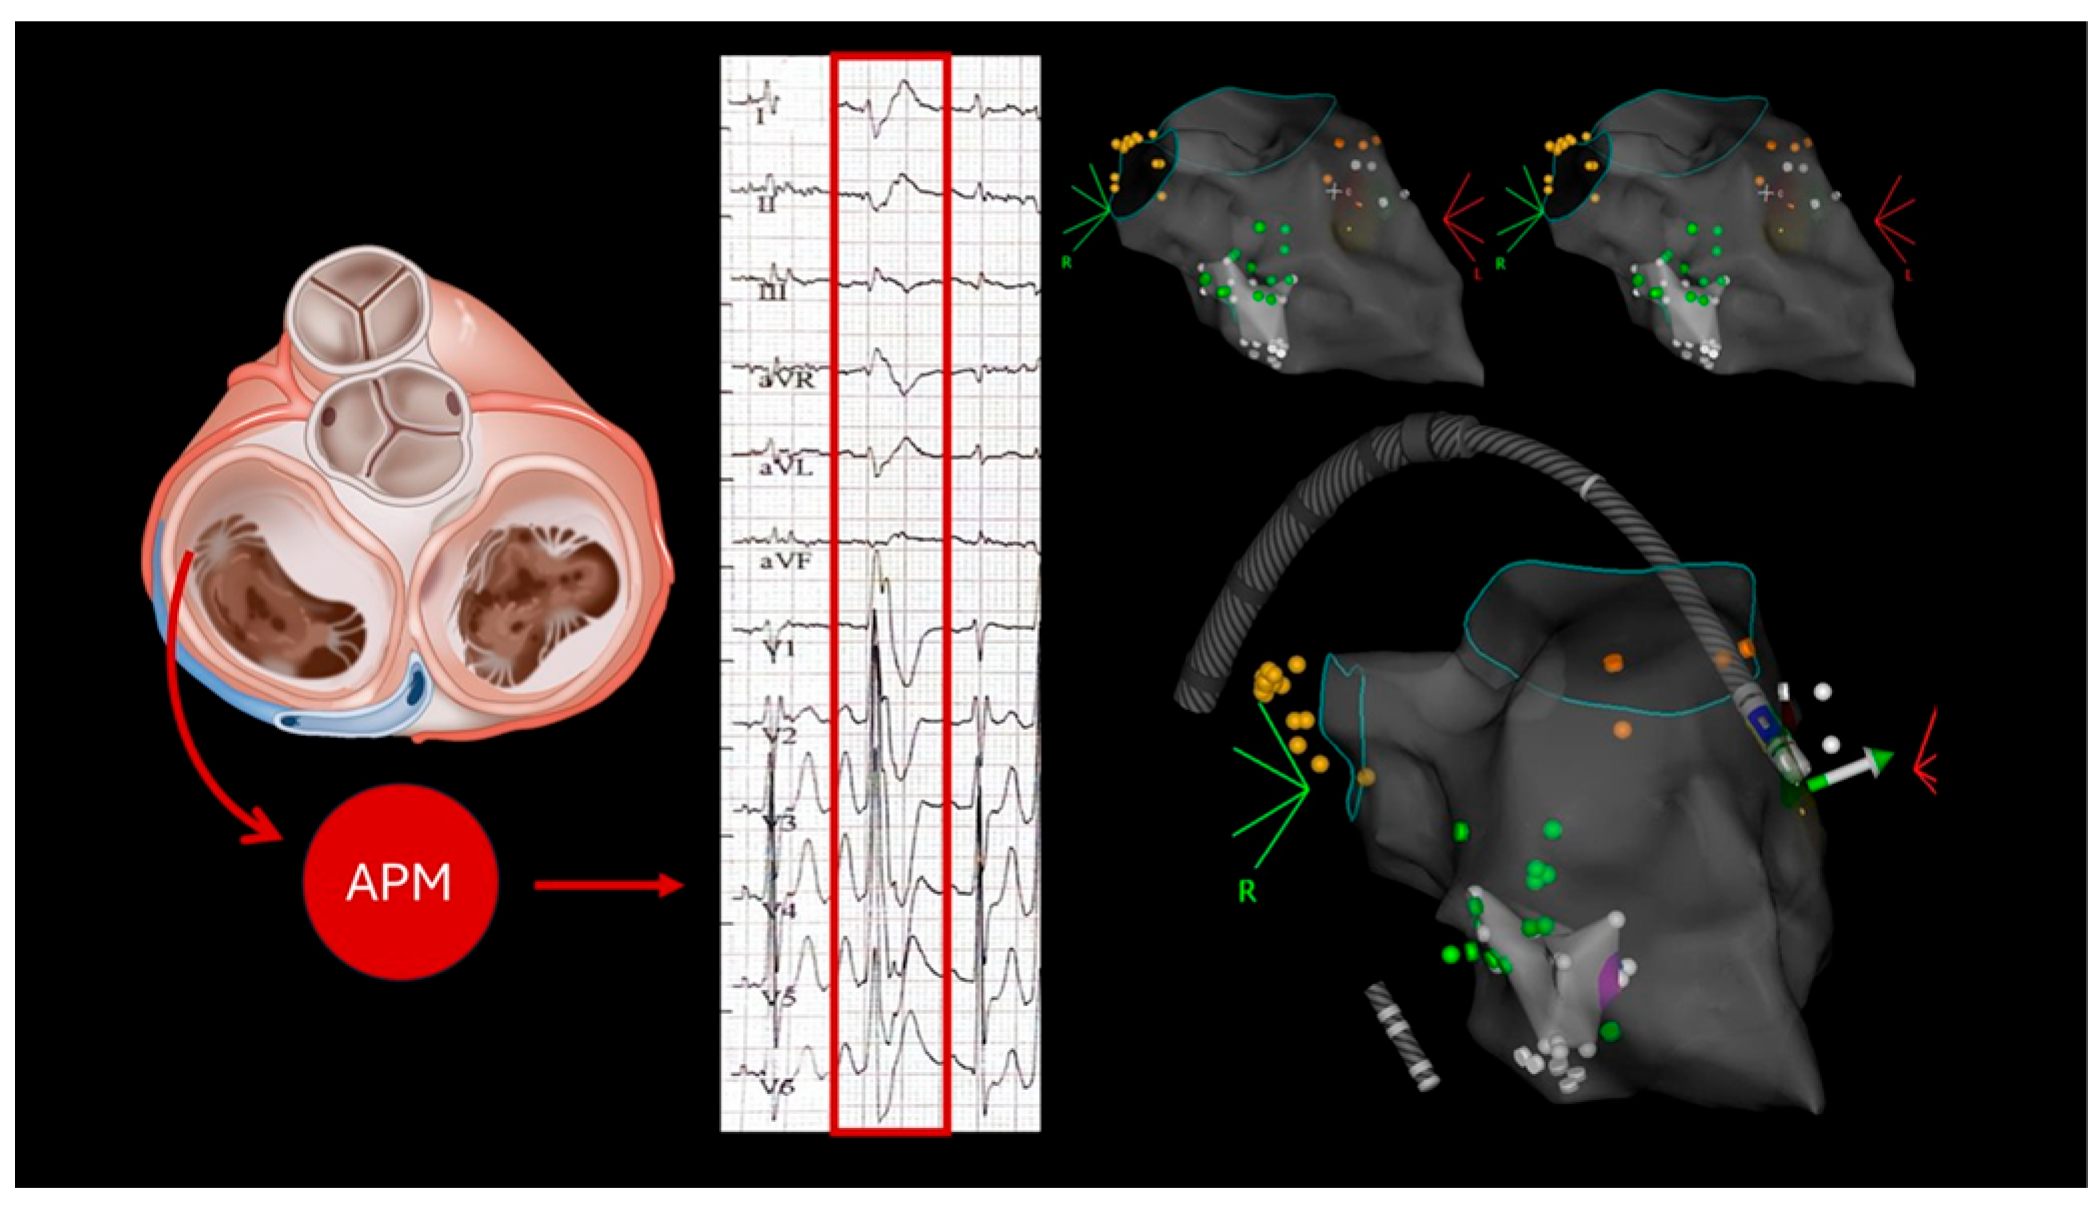

2.2. Case 2